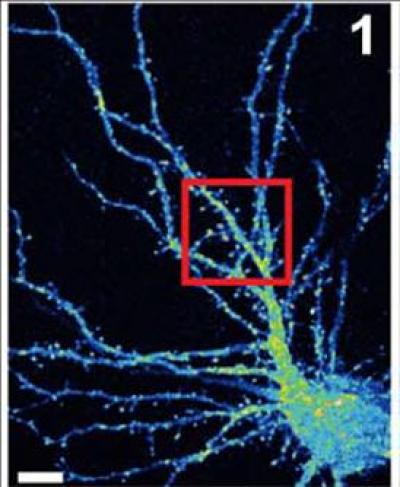

Professor Linda Van Aelst of Cold Spring Harbor Laboratory (CSHL) has been scrutinizing how the normal version of a protein called OPHN1 helps enable excitatory nerve transmission in the brain, particularly at nerve-cell docking ports containing AMPA receptors (AMPARs). Her team's new work, published June 24 in the Journal of Neuroscience , provides new mechanistic insight into how OPHN1 defects can lead to impairments in the maturation and adjustment of synaptic strength of AMPAR-expressing neurons, which are ubiquitous in the brain and respond to the excitatory neurotransmitter glutamate.

The new discovery shows how OPHN1 is involved in the trafficking of AMPARs, an essential feature of plasticity in neurons. Neurons move receptors away from synapses into their interior and then back to the surface of synapses to control connection strength. At the synaptic surface, receptors provide an opportunity for the docking of neurotransmitters, in this case glutamate molecules. After a cell has fired, surface receptors are typically brought back into the interior, where they are recycled for future use.

Van Aelst's new experiments explain how OPHN1 in complex with another protein called Homer1b/c should normally interact with an area called the endocytic zone (EZ) to provide a pool of AMPARs to be brought to the synapse at a location called the post-synaptic density (PSD). When OPHN1 is mutated, the pool does not form and receptors needed for strengthening synapses are not available. Long-term potentiation is impaired.